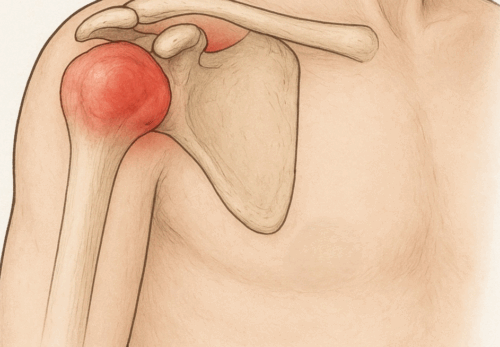

・肘関節だけでなく、肩・肩甲骨・体幹の連動性を高めるための施術